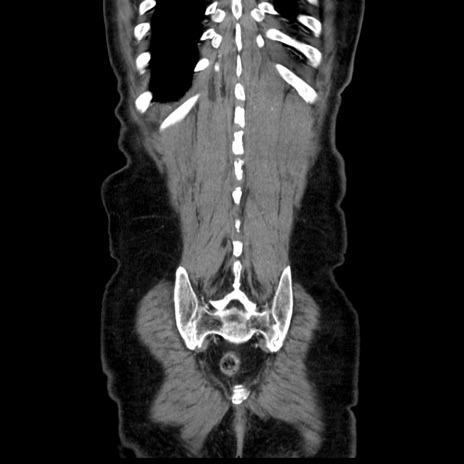

横断像